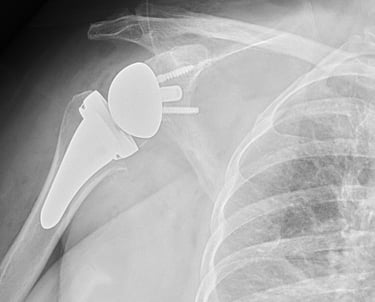

Chirurgia di Spalla e Gomito

Eseguo visite specialistiche, trattamenti conservativi e interventi specialistici sulla spalla e sul gomito, sia artroscopici sia a cielo aperto, per il trattamento delle principali patologie ortopediche e traumatiche di queste articolazioni.

Artrosi di spalla (Gleno-Omerale)